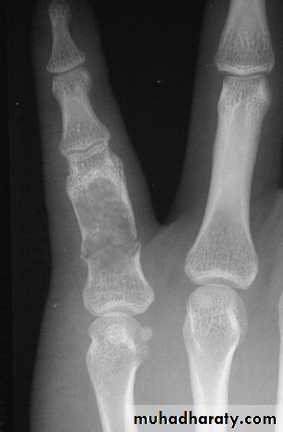

More in tubular bones of handAccidentally or pain / pathologic #

XR : lytic lesion + flecks of calcification

Malignant risk : 2%

Rx : curettage + bone graftPicture 4. Frontal radiograph of the right thigh demonstrates coarse calcifications in the distal femur.